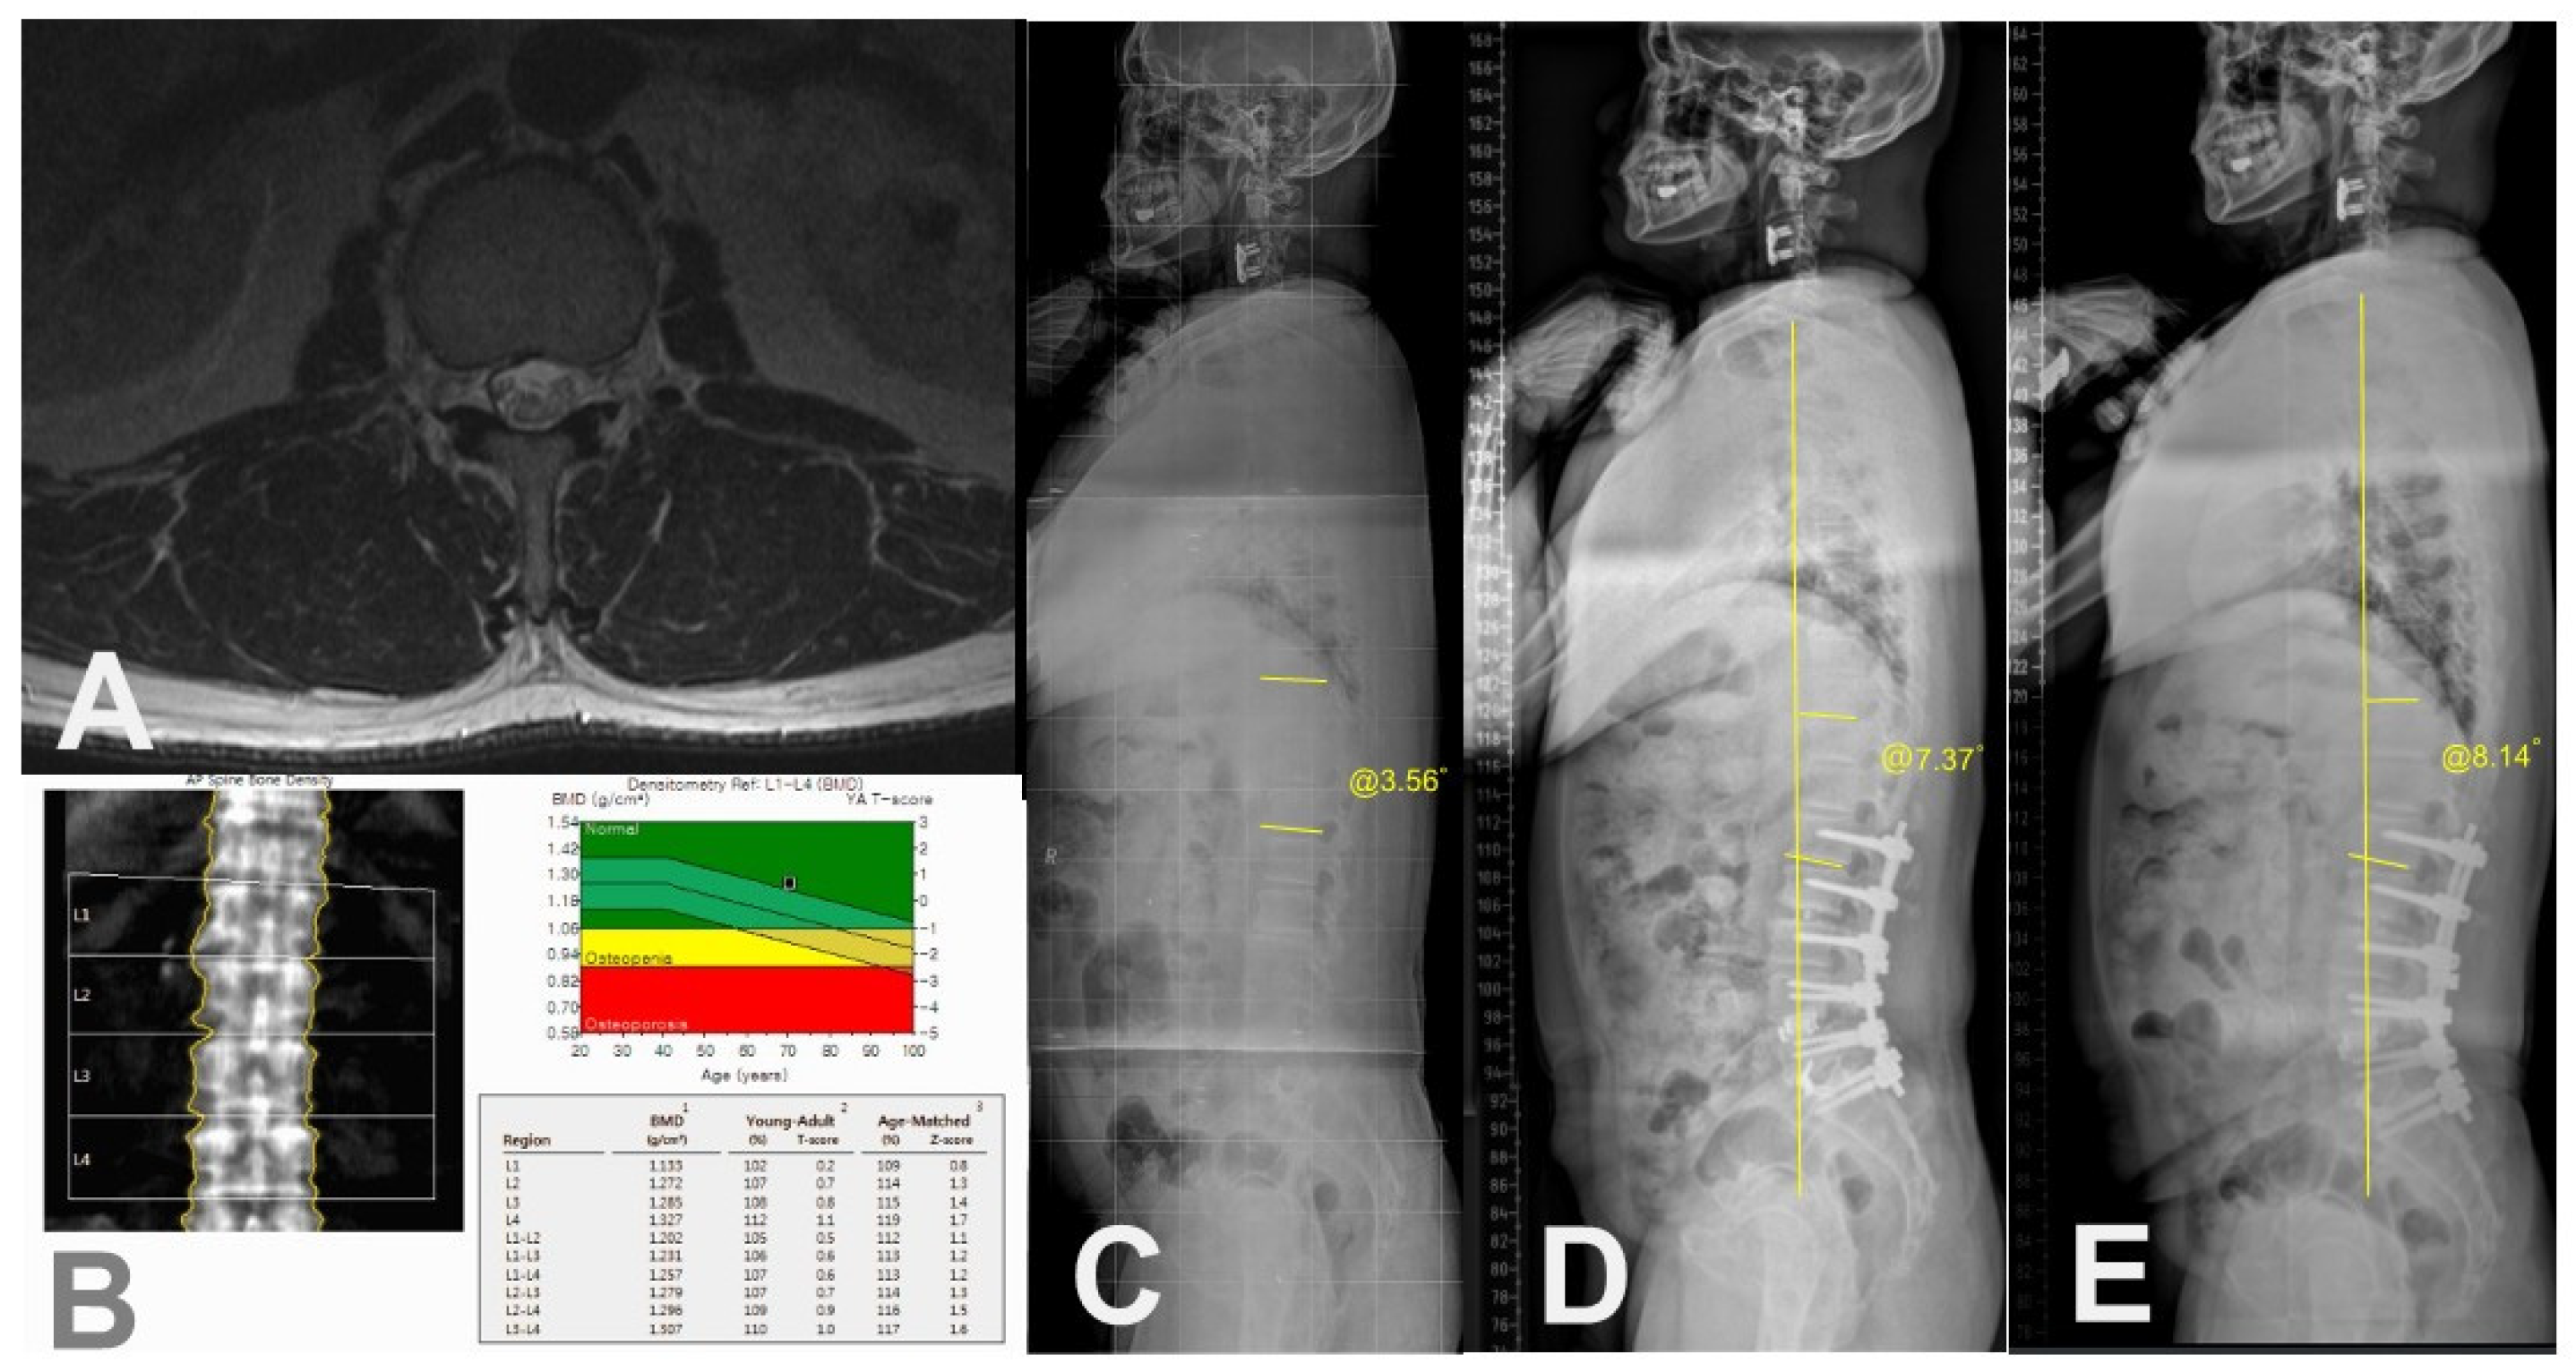

Figure 5.

A case of a 73-year-old female patient without PJK. (A) Preoperative axial T2-weighted magnetic resonance image showing erector spinae muscle with minimal fat infiltration at T12-L1 level. (B) Preoperative BMD showing no osteoporosis. (C) Preoperative whole spine standing lateral radiograph showing PJA of 3.56°. (D) Postoperative 3-month whole spine standing lateral radiograph showing PJA of 7.37°. (E) Postoperative 3-year standing lateral whole spine radiograph showing PJA of 8.14° with maintained C7SVA.